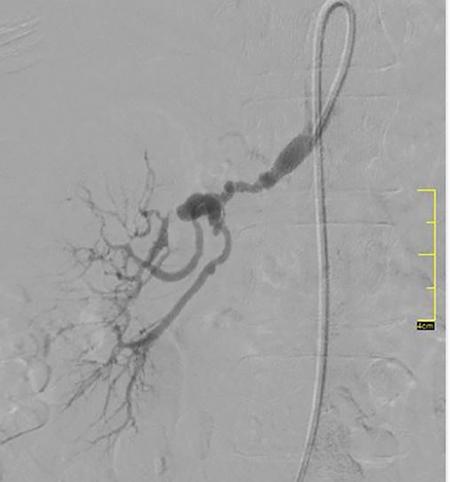

Vikash Jain Renal artery stenosis (RAS) may result in refractory hypertension, progressive renal insufficiency and cardiovascular complications such as refractory heart failure, flash pulmonary edema and acute coronary syndrome. There is overwhelming evidence that hypertension associated with a haemodynamically significant atherosclerotic RAS is better controlled with fewer medicines following renal revascularization. A meta-analysis of small series indicated that renal function is improved in about 30% and stabilized in 38% with an overall favourable response of 68% following percutaneous transluminal renal angioplasty (PTRA) in atherosclerotic renal artery stenosis (ARAS). Several randomized controlled trials have shown no difference in outcomes with optimal medical therapy (OMT) and PTRA compared with OMT alone in terms of BP control, preservation of renal function or major cardiovascular events. However, each of these trials had significant design flaws that ranged from variability in inclusion and exclusion criteria, inconsistent definitions of improvement that limit their applicability in day to day practice, making the selection of patients for renal artery stenting a controversial topic. These trials excluded patients with resistant hypertension, accelerated hypertension, advanced kidney disease, history of refractory heart failure or a recent acute coronary syndrome. This patient group who was most likely to be benefitted by PTRA was excluded in the trials. Atherosclerosis is the most common cause (90%) of RAS in adults, with fibromuscular dysplasia (FMD) being more common in younger female patients. ARAS is the most common cause of secondary hypertension affecting 25%–35% of the patients with secondary hypertension. Approximately 25% of elderly patients with chronic kidney disease (CKD) were found to have unsuspected ARAS. In elderly population referred for coronary angiography and having coexistent hypertension, haemodynamically significant RAS (>70%) was found in more than 20% of patients. FMD is a nonatherosclerotic, noninflammatory, congenital condition that leads to dissection, aneurysm or stenosis of medium-sized artery predominantly affecting renal, carotid and femoral. It usually involves mid to distal portion of the renal artery. On angiography, FMD shows characteristic ‘string of pearls’ appearance or less commonly concentric smooth stenosis (Fig. 10.20.1). Renal FMD has a female preponderance, and can lead to HTN, which is preferentially treated with balloon angioplasty. CLINICAL FINDINGS ASSOCIATED WITH RENOVASCULAR DISEASE